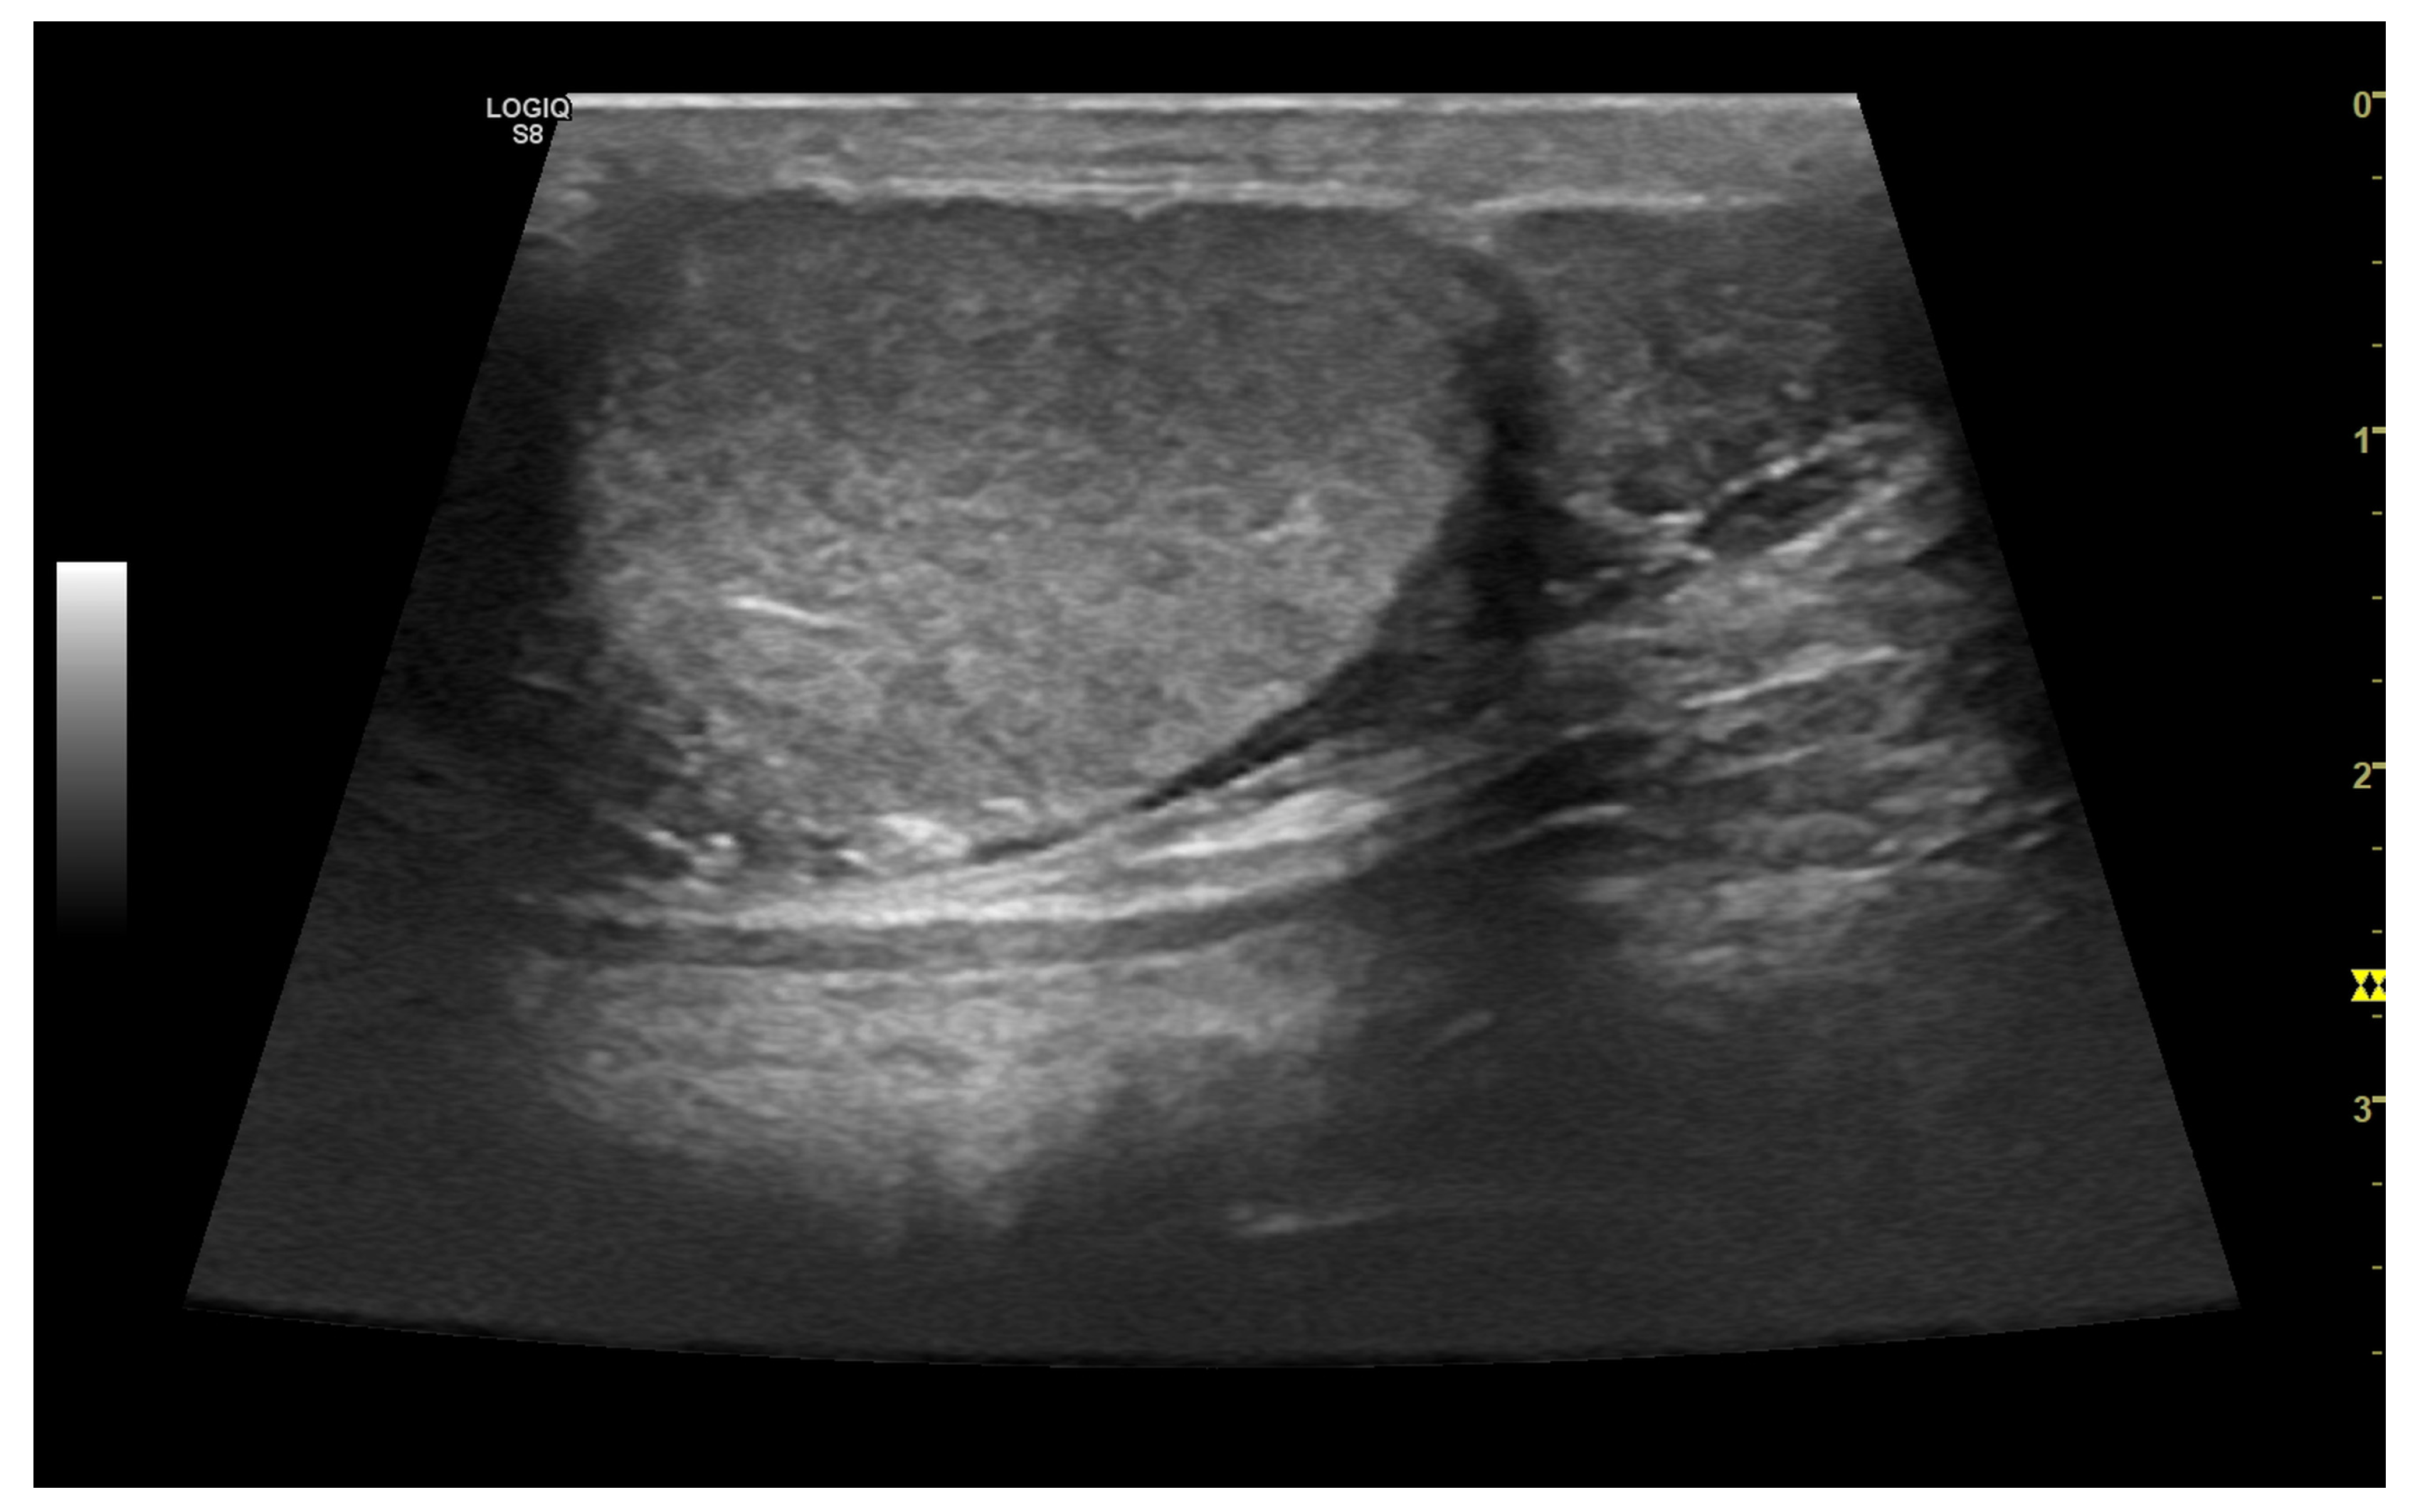

3.4.1. Intratesticular Diseases

3.4.2. Extratesticular Diseases